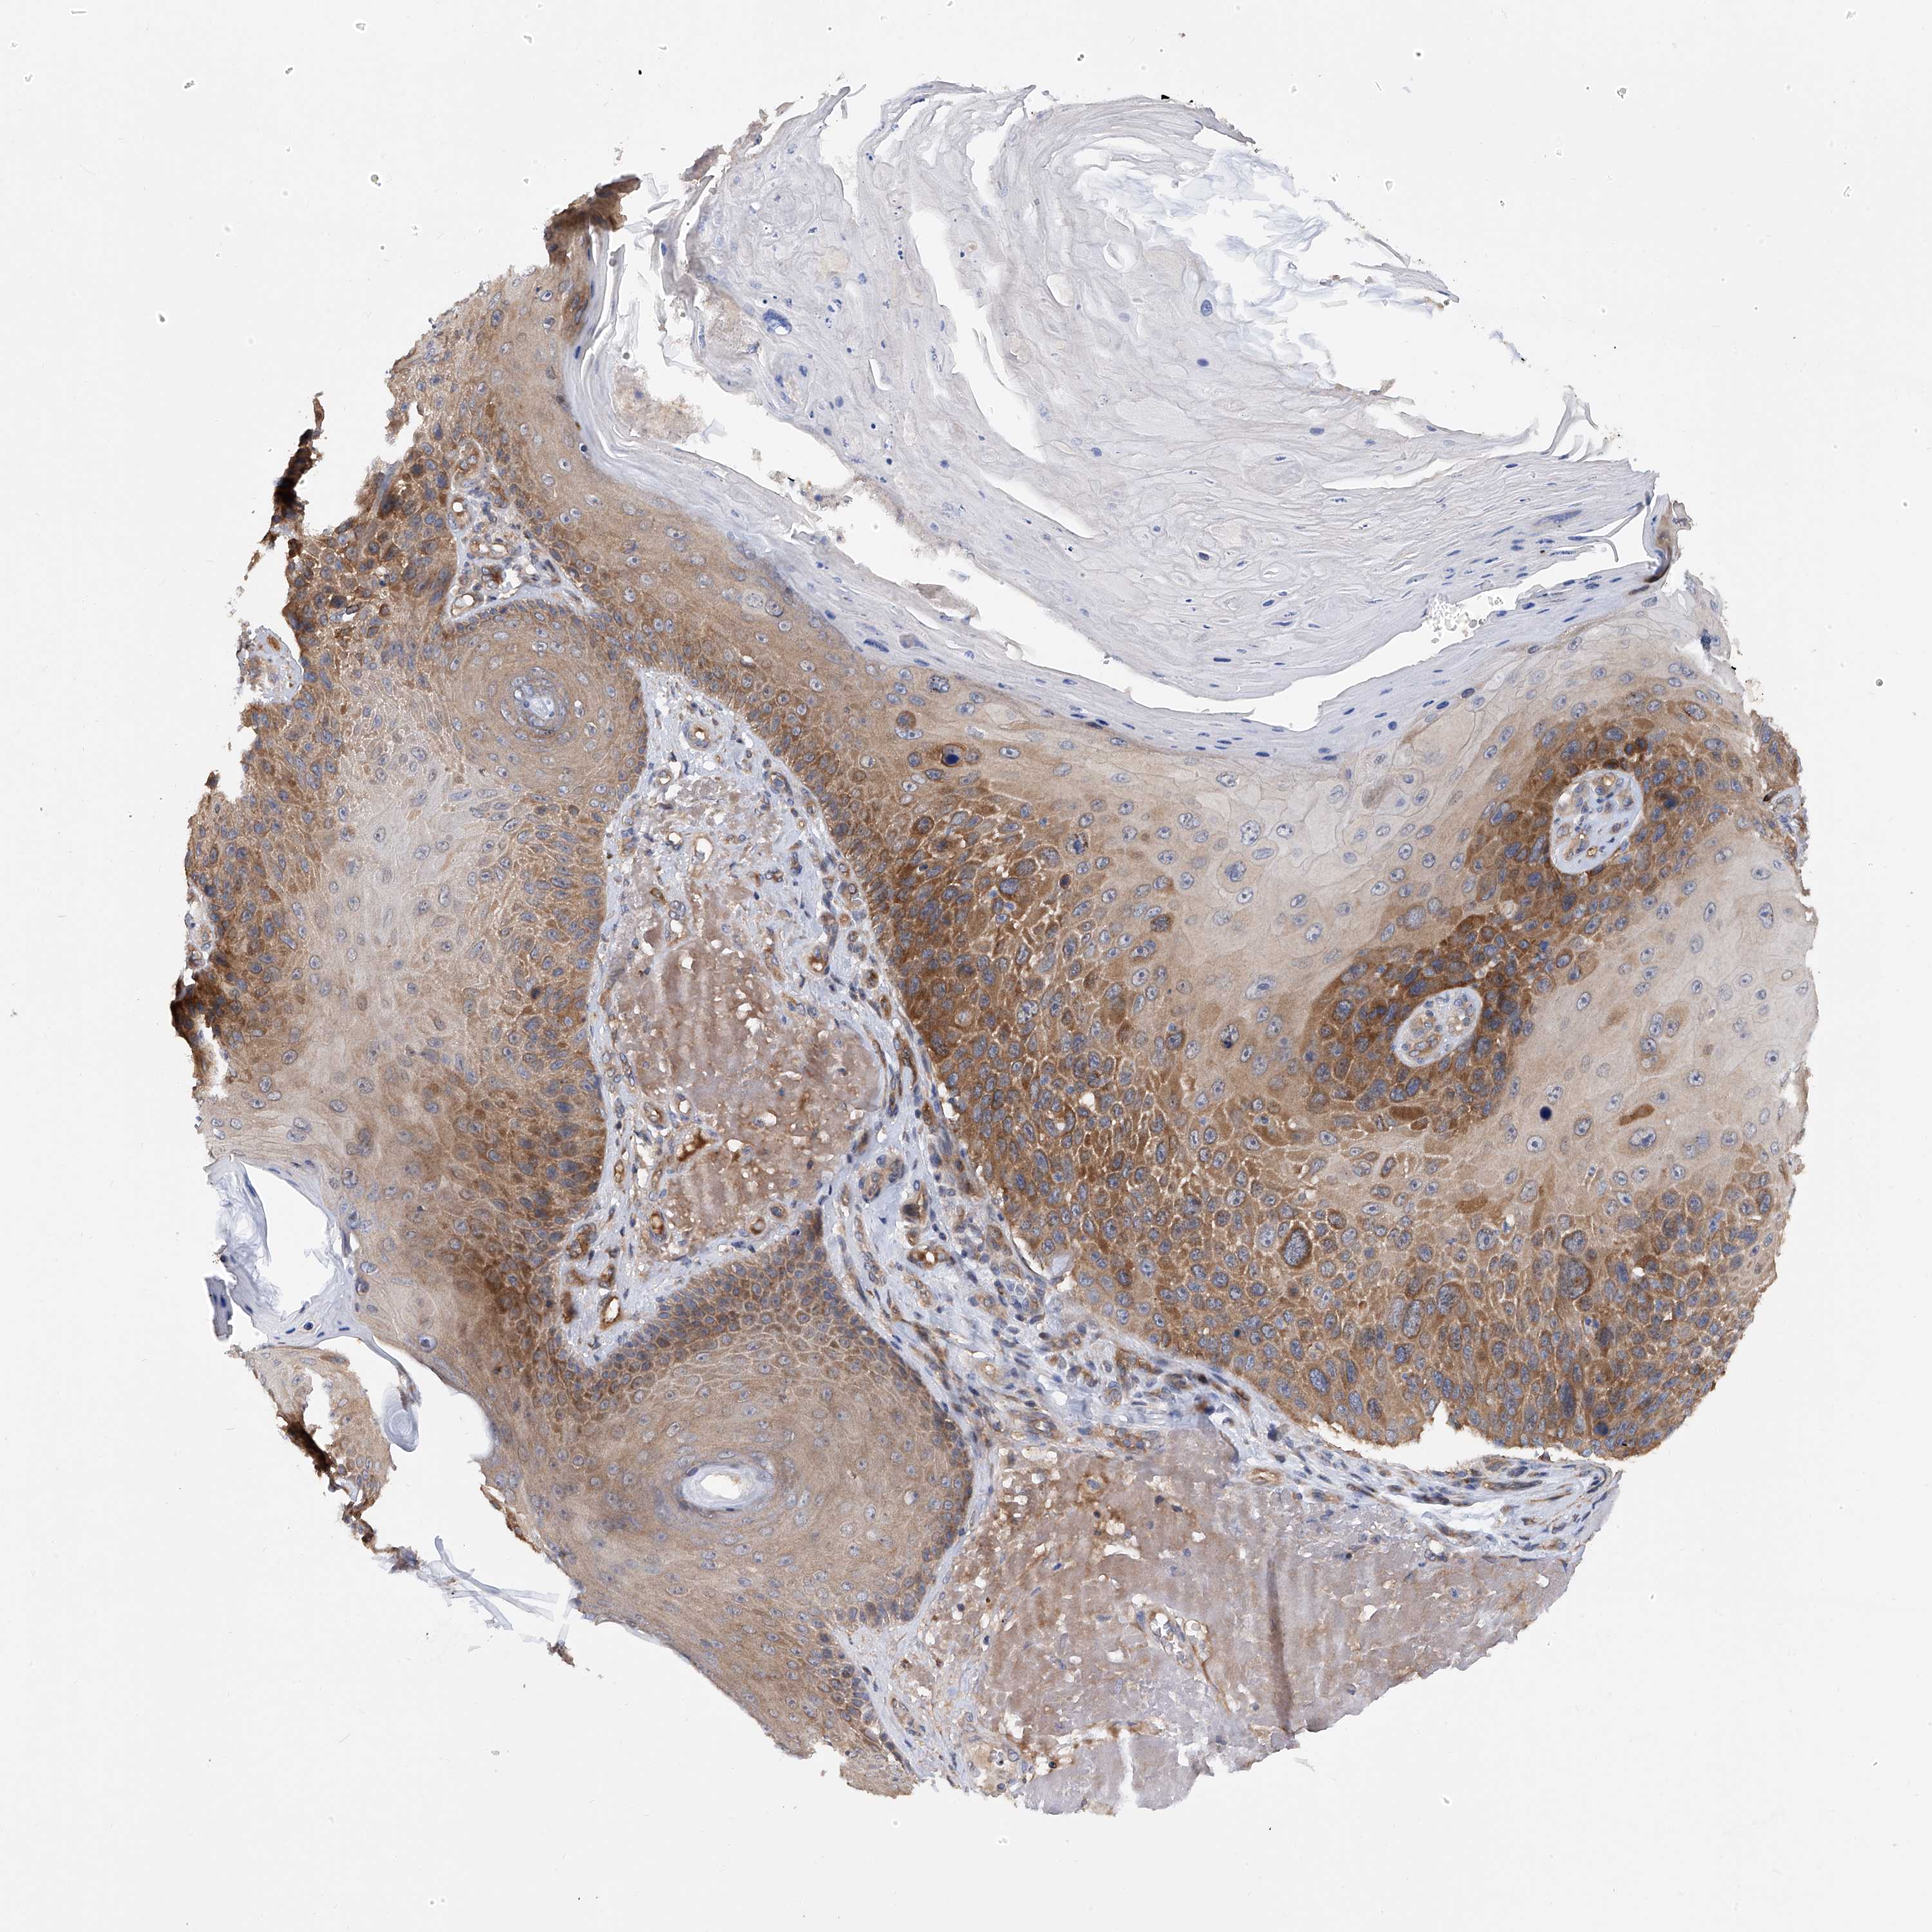

Basal cell and squamous cell cancer

SKIN CANCER - Protein expressioni

A mouse-over function shows sample information and annotation data. Click on an image to view it in a full screen mode. Samples can be filtered based on level of antibody staining by selecting one or several of the following categories: high, medium, low and not detected. The assay and annotation is described here.

Antibody stainingi

Antibody staining in the annotated cell types in the current human tissue is reported as not detected, low, medium, or high, based on conventional immunohistochemistry profiling in selected tissues. This score is based on the combination of the staining intensity and fraction of stained cells.

Each image is clickable and will lead to virtual microscopy that enables deeper exploration of all samples and also displays staining intensity scores, fraction scores and subcellular localization as well as patient and tissue information for each sample.

Antibody HPA030145

Staining

High

Medium

Low

Not detected

Intensity

Strong

Moderate

Weak

Negative

Quantity

>75%

75%-25%

<25%

None

Location

Nuclear

Cytoplasmic/membranous

Cytoplasmic/membranous,nuclear

Squamous cell carcinoma, metastatic, NOS